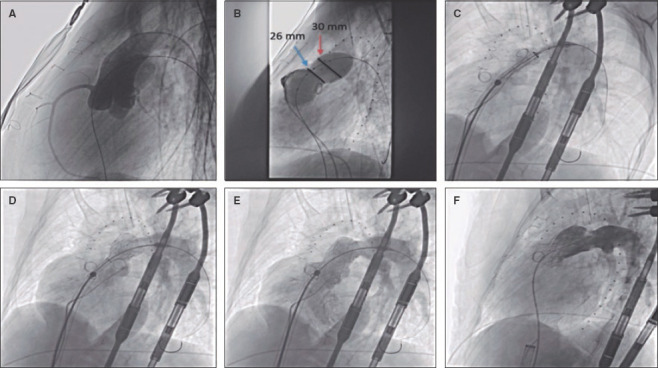

Abstract Image